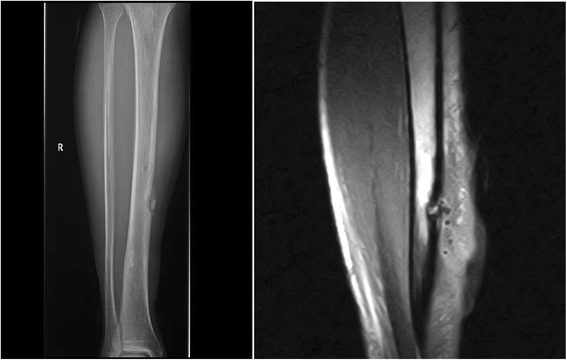

Case presentation: We report a case of a 49-year-old Spanish man with recurrent bilateral granulomatous uveitis and a fistulous nodular lesion in the left pre-tibial region (scar granuloma) on the site of an 8-year-old scar. He presented with bilateral hilar adenopathies and elevation of inflammatory markers and angiotensin-converting enzyme. A histologically confirmed sarcoid of the tibia with a radiologic appearance unusual for long tubular bone involvement was observed. He also had bilateral ophthalmologic involvement.